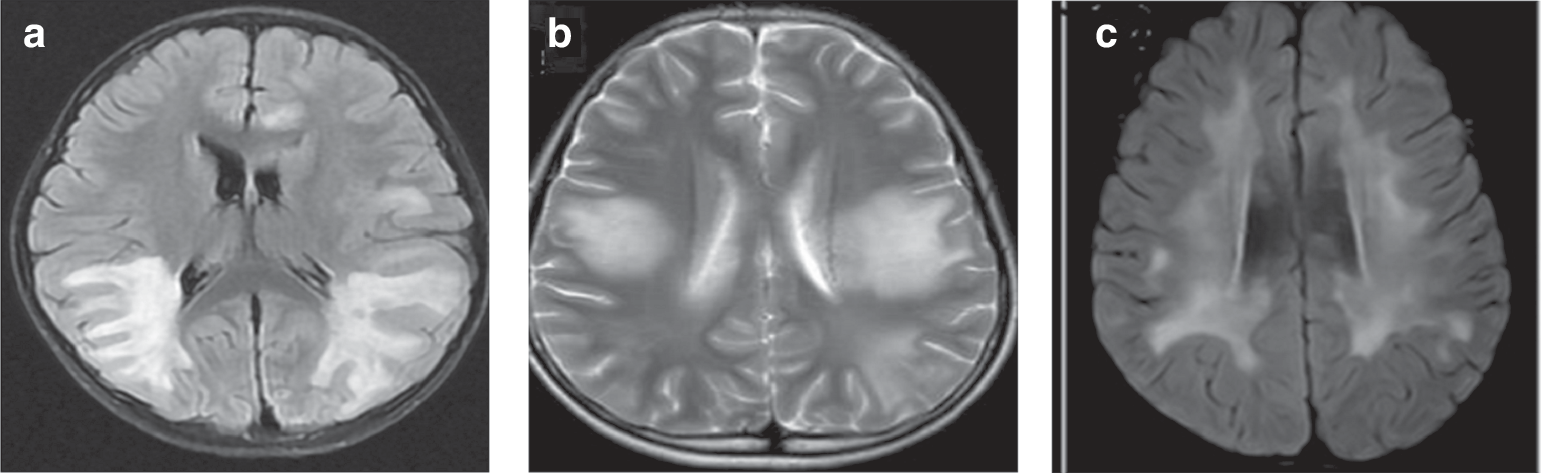

Fig. 3: MRI features of cerebral leukodystrophy-like phenotype.

a Paraventricular symmetric white matter lesions. b Large supratentorial symmetric cerebral white matter lesions. c Diffuse subcortical white matter changes.